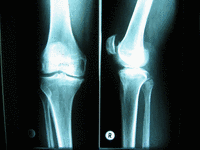

Diagnostik

Neben einer klinischen Untersuchung steht die Röntgenuntersuchung an erster Stelle zur Diagnosestellung. Weitere Untersuchungsmethoden wie MRT und CT-Aufnahmen sind hierbei von untergeordneter Bedeutung.